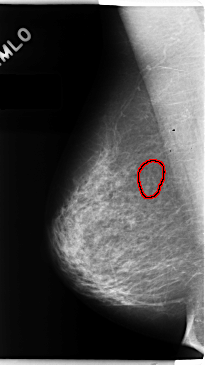

C_0151_1.RIGHT_MLO

RIGHT_MLO LINES 4736 PIXELS_PER_LINE 2656 BITS_PER_PIXEL 12 RESOLUTION 50 OVERLAY

FILE: C_0151_1.RIGHT_MLO.OVERLAY

TOTAL_ABNORMALITIES 1

ABNORMALITY 1

LESION_TYPE CALCIFICATION TYPE PLEOMORPHIC DISTRIBUTION CLUSTERED

ASSESSMENT 4

SUBTLETY 3

PATHOLOGY MALIGNANT

TOTAL_OUTLINES 1

BOUNDARY